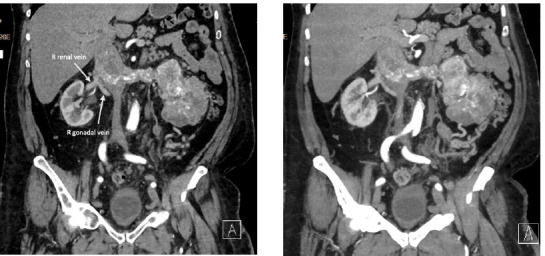

This article is a case report of a 62-year-old male with a left-sided renal cell carcinoma (RCC) with a level II inferior vena cava (IVC) thrombus and caval occlusion. He was managed with open left radical nephrectomy and juxtarenal cavectomy. To preserve right renal venous drainage, the right renal vein was anastomosed to the right gonadal vein. He has not had any renal functional decline or disease recurrence with 3 years of follow-up. The focus of this article is to discuss this distinctive method for vascular reconstruction as an option for right renal venous drainage following left nephrectomy and juxtarenal cavectomy.